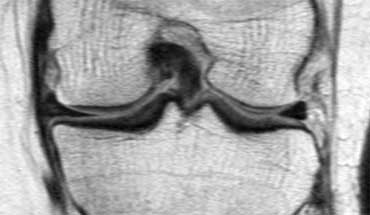

Bên trái là một trường hợp khác của sụn chêm ngoài bị lật.

- Lưu ý sừng trước rất lớn.

Phần trong là sừng sau đã bị di lệch. - Phần trong chạy vào hố gian lồi cầu.

- Phần bị di lệch được nhìn thấy rõ ràng như là ‘cấu trúc thứ ba’

trong hố gian lồi cầu. - Điểm nối với phần còn lại của sừng sau.

- Điểm nối với phần còn lại của sừng sau.

- Phần còn lại rất nhỏ của sừng sau.